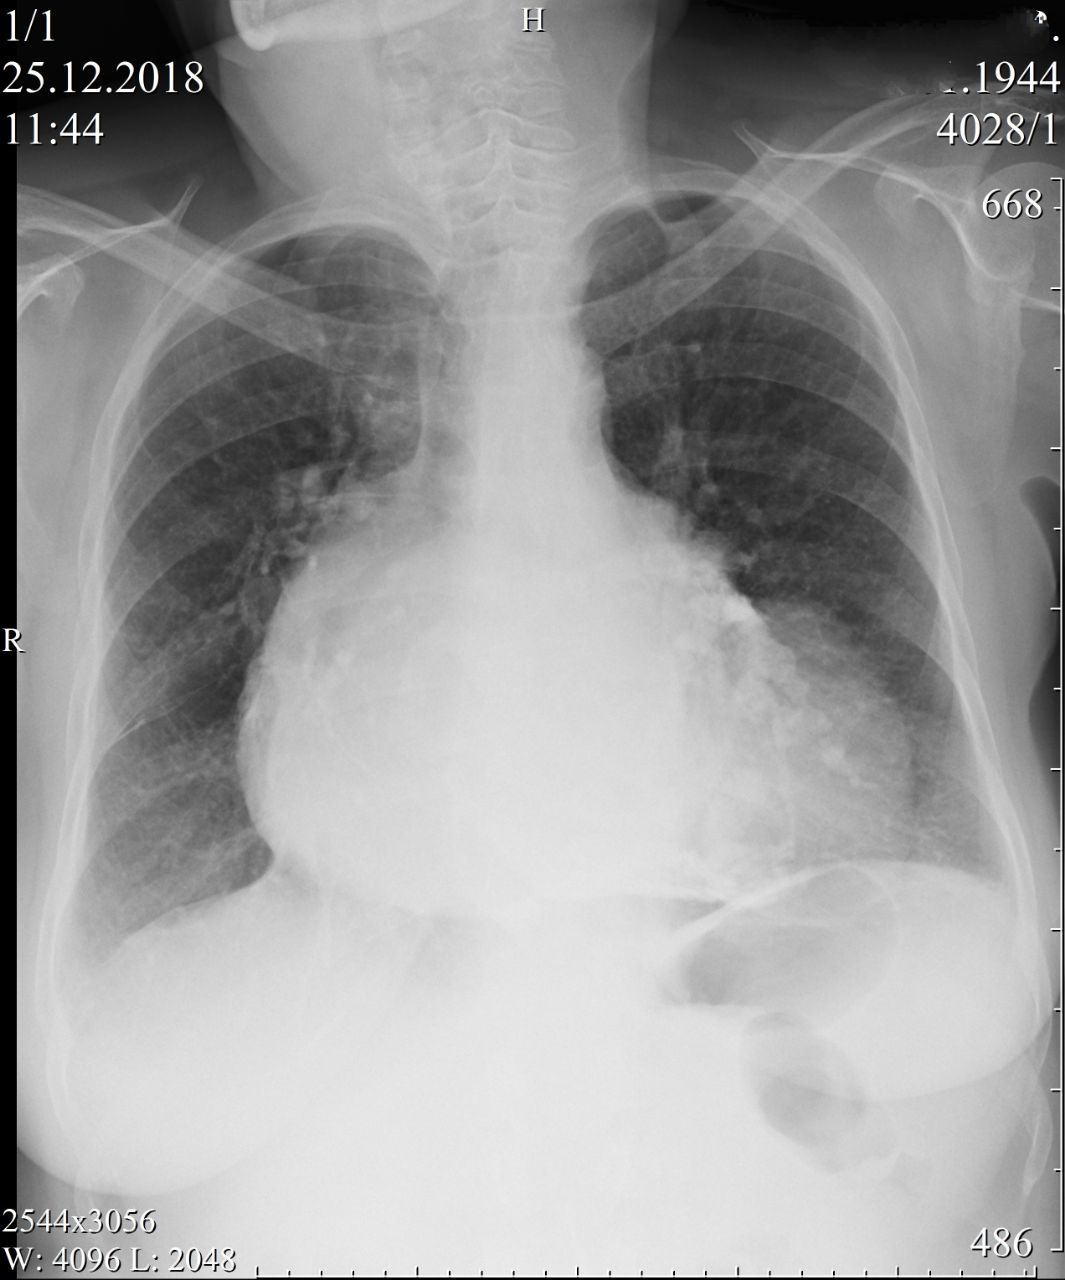

Доброе утро коллеги. Недавно в п-ку пришла пациентка... Я даже не поленился притащить флэшку, чтобы скинуть изображения в оригинале. Не фоткать с экрана. Оцените вот, какая красота!

В левом желудочке предположил аневризму. Ну и панцирное сердце.

Перикардиальная киста

Да, дооолгий перикардит приводит к отложению Са в сердечной сумке.

А хорошая версия. Пожалуй, она мне нравится даже больше аневризмы. Впишу через слэш, как дифдиагноз. Спасибочки.

Между панцирным и кистой